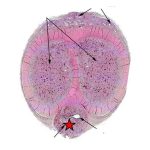

4陰莖為男性重要的性器官,具有性交功能,並有排尿和射精作用。陰莖主要由兩個陰莖海綿體和一個尿道海綿體組成,外包以基筋膜和皮膚。 一、陰莖結構包括哪些部位 陰莖結構一般包括陰莖頭、陰莖體,還有陰莖根,在平時需要加以護理,防止出現損傷。 1、陰莖頭:陰莖頭屬於陰莖主要結構組成,屬於陰莖...

陰莖為男性重要的性器官,具有性交功能,並有排尿和射精作用。陰莖主要由兩個陰莖海綿體和一個尿道海綿體組成,外包以基筋膜和皮膚。 一、陰莖結構包括哪些部位 陰莖結構一般包括陰莖頭、陰莖體,還有陰莖根,在平時需要加以護理,防止出現損傷。 1、陰莖頭:陰莖頭屬於陰莖主要結構組成,屬於陰莖...